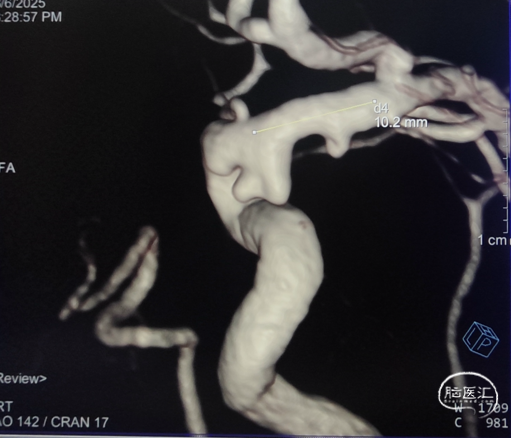

术前影像

右侧颈内动脉3D造影:右侧颈内动脉C6动脉瘤。

右侧颈内动脉造影重建:右侧颈内动脉动脉瘤。